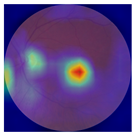

| No. | Fundus Image | Grad-CAM | Group | PRS | CNN | CNN+ML |

|---|---|---|---|---|---|---|

| 1 |  |  | Control | −1.07 | −0.57 | −1.95 |

| 2 |  |  | Control | −0.30 | −0.85 | −1.50 |

| 3 |  |  | Control | −3.12 | −1.53 | −1.83 |

| 4 |  |  | AMD | −0.99 | 0.29 | −0.86 |

| 5 |  |  | AMD | −0.23 | −0.29 | −0.66 |

| 6 |  |  | AMD | 0.17 | 1.31 | −0.75 |

| 7 |  |  | AMD | −0.43 | 1.16 | −0.48 |